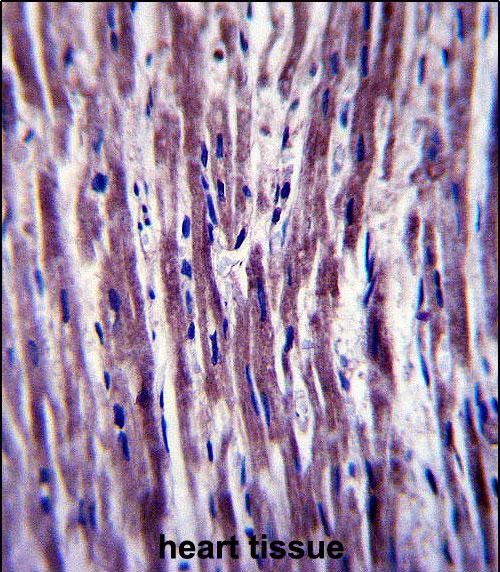

| IHC | 1/100-1/500 | Human,Mouse,Rat |